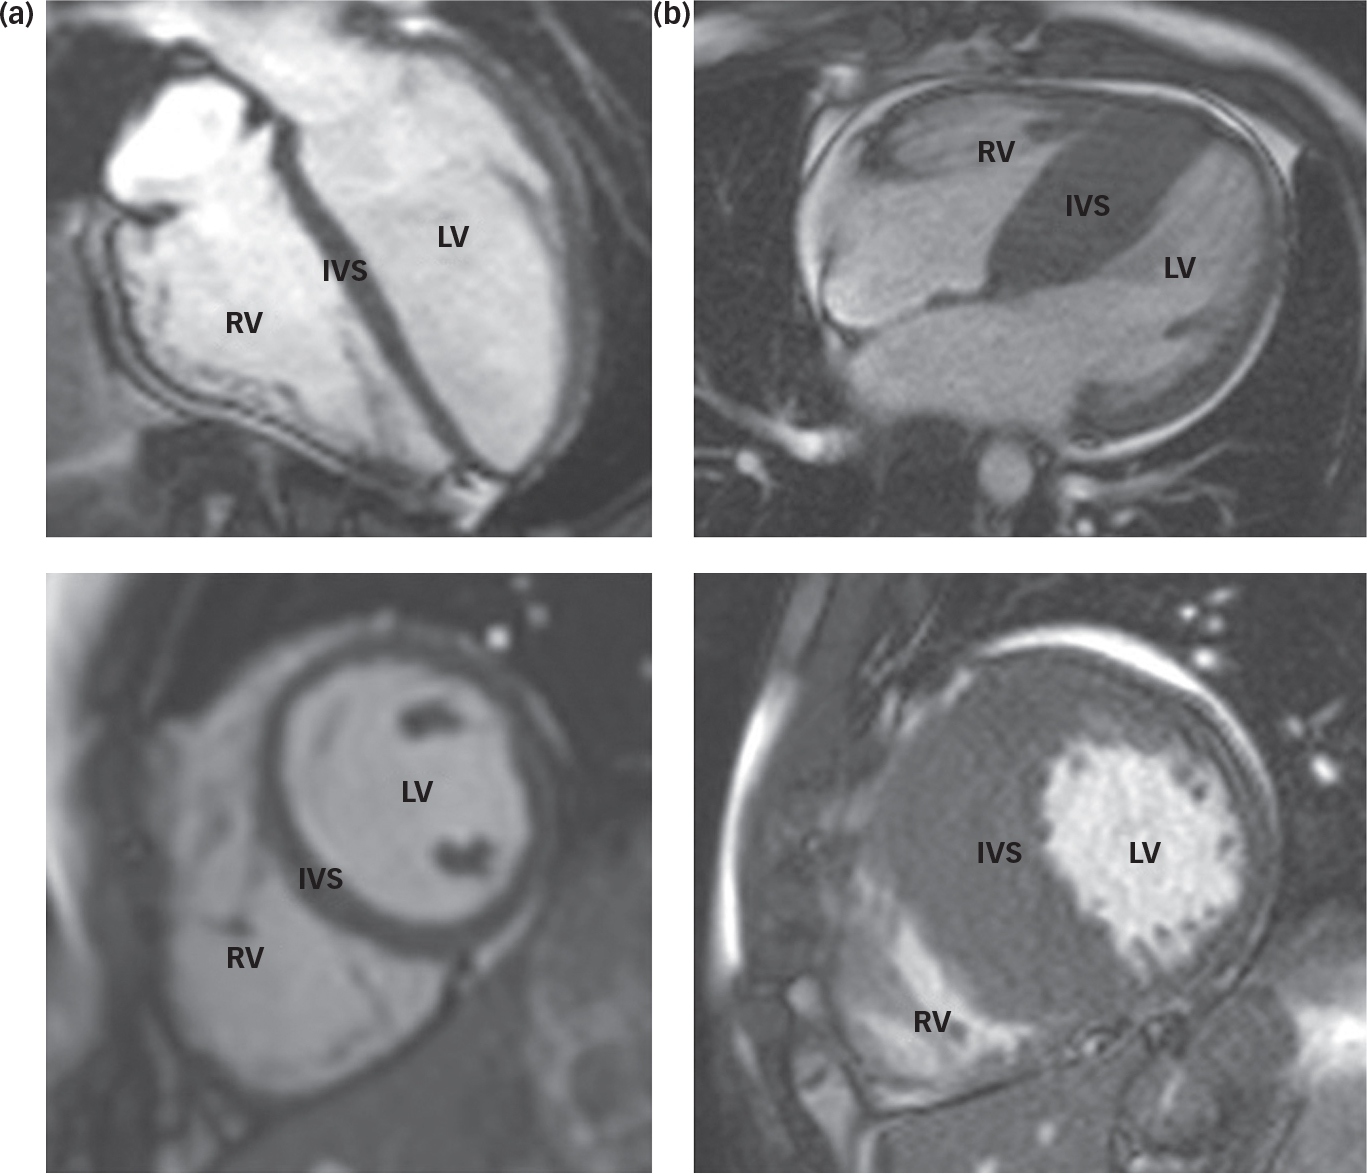

The patient was a 36-year-old British male of Iranian decent with a diagnosis of treatment-resistant schizophrenia. He was single, unemployed and living with his family. He was referred for a trial of clozapine in the context of an established diagnosis of HCM (Fig. 1). At the time of admission, he presented with multimodal hallucinations, thought disorder, delusional beliefs and psychosomatic symptoms; he had no cardiovascular symptoms. On admission, he scored 40 on the Psychotic Symptom Rating Scales (PSYRATS)Reference Haddock, McCarron, Tarrier and Faragher 9 and 80 on the Depression Anxiety Stress Scale (DASS).Reference Lovibond and Lovidbond 10 He had previously trialled a number of antipsychotic agents with limited improvement, including aripiprazole, paliperidone, amisulpride and risperidone. Flupentixol and olanzapine had been moderately successful in treating his positive symptoms, but had to be stopped because of adverse motor effects. At the time of admission, he was on amisulpride 800 mg and sertraline 100 mg for low mood.

Fig. 1 Cardiac magnetic resonance images of a normal heart (a) and a heart demonstrating hypertrophic cardiomyopathy (b). Note the significant increase in muscle mass at the intraventricular septum (IVS) in the abnormal heart (b). LV – left ventricle; RV – right ventricle.

Relevant past medical history includes the diagnosis of HCM, made 3 years prior following the finding of an abnormal ECG. Further diagnostic investigations had included TTE, 24-h Holter monitoring and cardiovascular magnetic resonance imaging (CMR). During the 3-year follow-up period, the patient had been asymptomatic and was not felt to be at significant risk of sudden cardiac death (Table 1). He was taking bisoprolol 7.5 mg daily to treat hypertension – this being the agent of choice in those with HCM to help ameliorate the potential risk of arrhythmic demise and outflow obstruction associated with HCM. Other cardiovascular risk factors include a 17 pack/year smoking history and hypercholesterolaemia controlled with atorvastatin 40 mg daily.